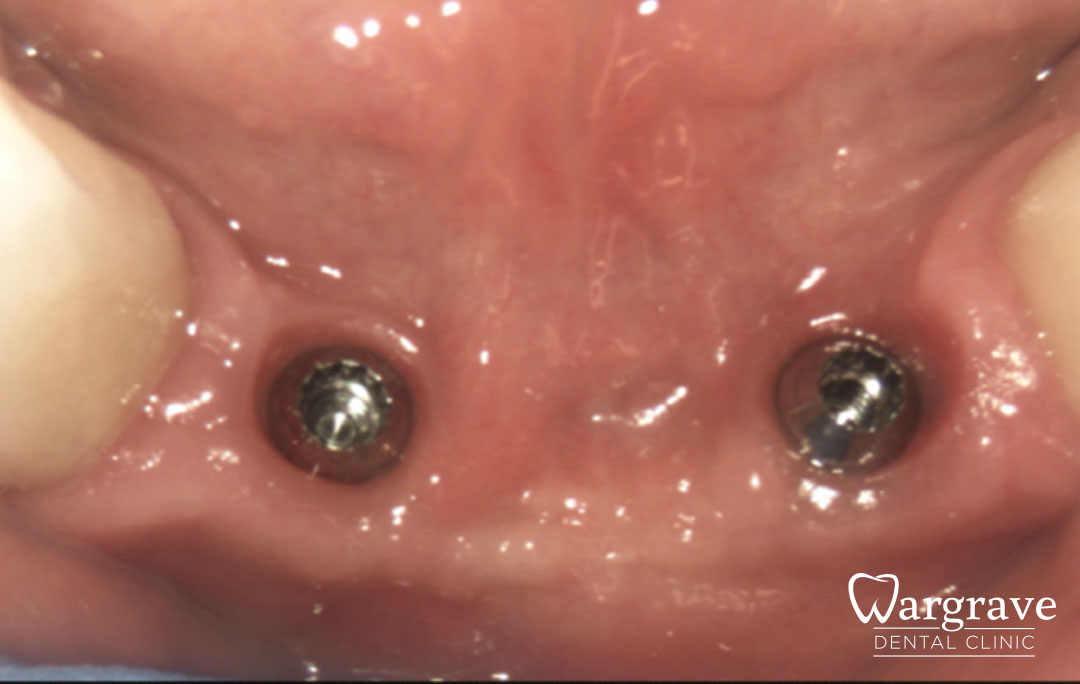

After

This patient presented with a very narrow anterior mandible and insufficient bony width for dental implants. An extensive grafting procedure was carried out. Several months later the site was restored with a four unit fixed Implant Bridge on two implants

All stages of surgical and restorative work by Mr RS Khurana